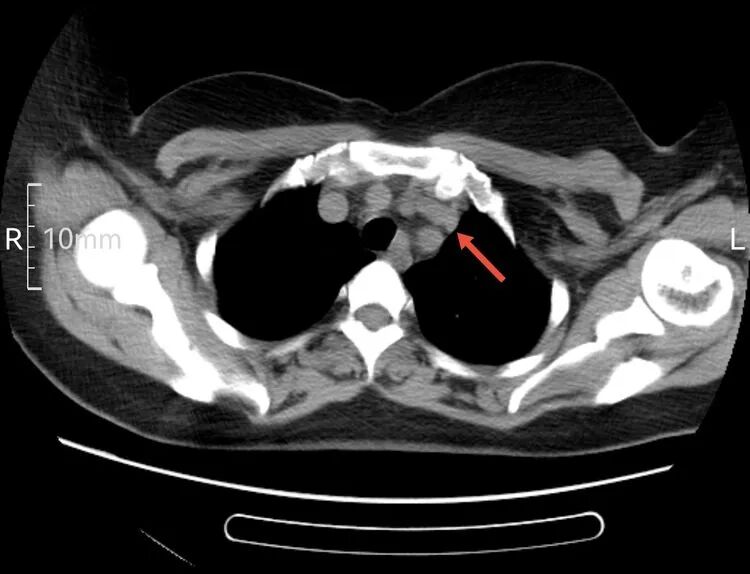

以下是患者的CT表现:

为什么建立双输液通道输液港 偶遇“双上腔静脉”_https://www.jmylbn.com_新闻资讯_第5张

箭头所指为左侧“上腔静脉”走行  虽然过程不寻常,但在血管造影辅助下显示其“真容”后,导管经左侧颈内静脉,避开变异的“左上腔静脉”并通过左侧头臂干,导管头端留置在正常的上腔静脉内。成功给予患者植入左侧胸壁港。